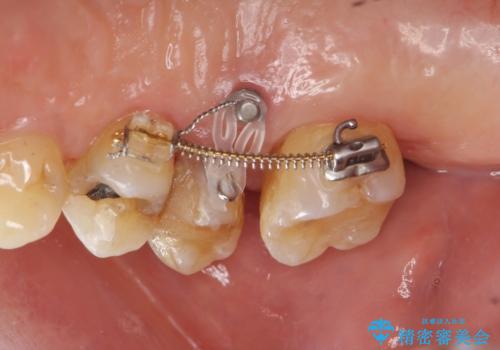

検査の結果、強い歯ぎしりによる歯の周囲の骨の吸収が認められたため歯槽骨の再生・歯周ポケットの除去・力に対抗する連結補綴・補綴前処置としての小矯正を計画します。

今回連結補綴を行うにあたり、歯周病の問題を解決するために再生療法・歯周ポケット除去手術を、またより歯の神経を保存し力に対抗できる環境を整えるために小矯正を行い精度の高いメタルボンドクラウンを製作することができました。